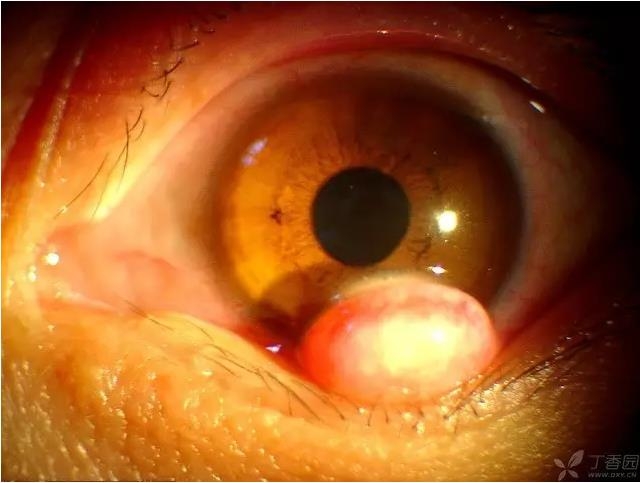

▼角膜皮样瘤

实用贴:眼科病例高清图片

▼角膜皮样瘤(不同的患者,弥散光照明)